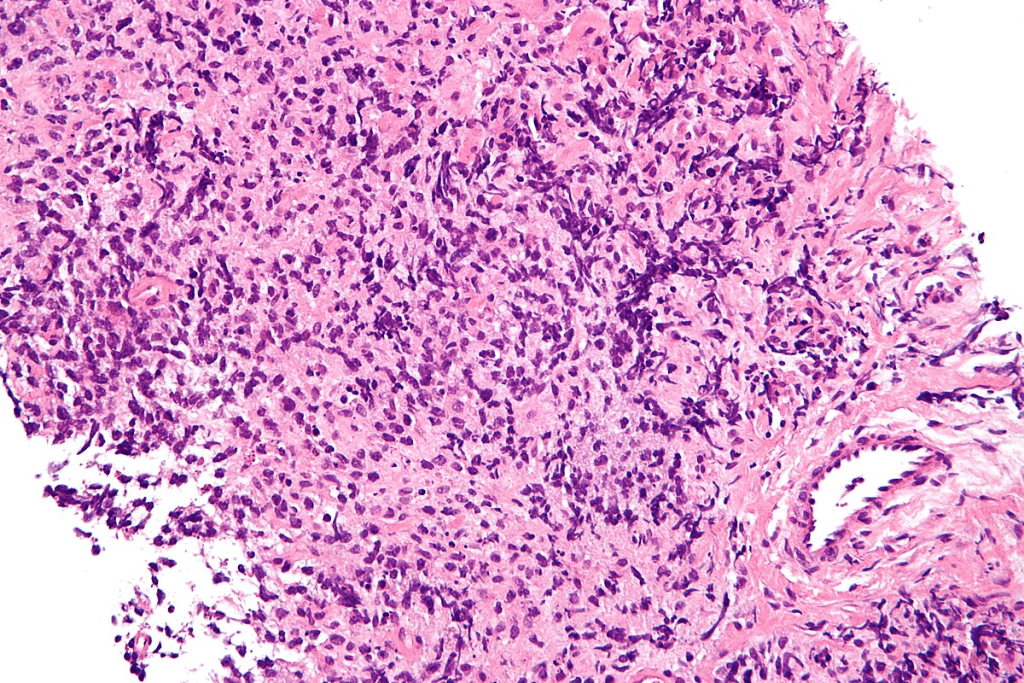

The first step in diagnosing CLL is blood tests. These tests check for lymphocytes, a type of white blood cell. A complete blood count (CBC) and flow cytometry are key for spotting CLL’s abnormal lymphocytes.

A bone marrow examination might also be done. It includes a biopsy and aspiration. These give detailed info on CLL’s effect on blood cell making.